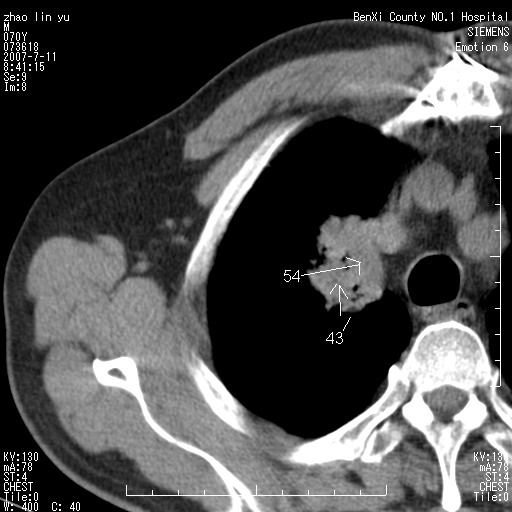

以下是引用王靖旗在2007-7-10 17:12:00的发言:[br] 男、70、咳嗽两个月,半年前换瓣手术,胸片未见异常,于昨天行x片发现右肺上野大片影,行ct扫描,这里是减薄图像,余肺正常。明天晚上会有增强扫描片,到时我会上传。[br][br] 冠状位请大家细看,应该是有意义的,[br][br] 请大家先看平扫发表意见。[br][br]

以下是引用zhangzhongshou在2007-7-10 21:43:00的发言:[br]右肺上叶周围型肺癌,以孤立型细支气管肺泡癌可能性大。